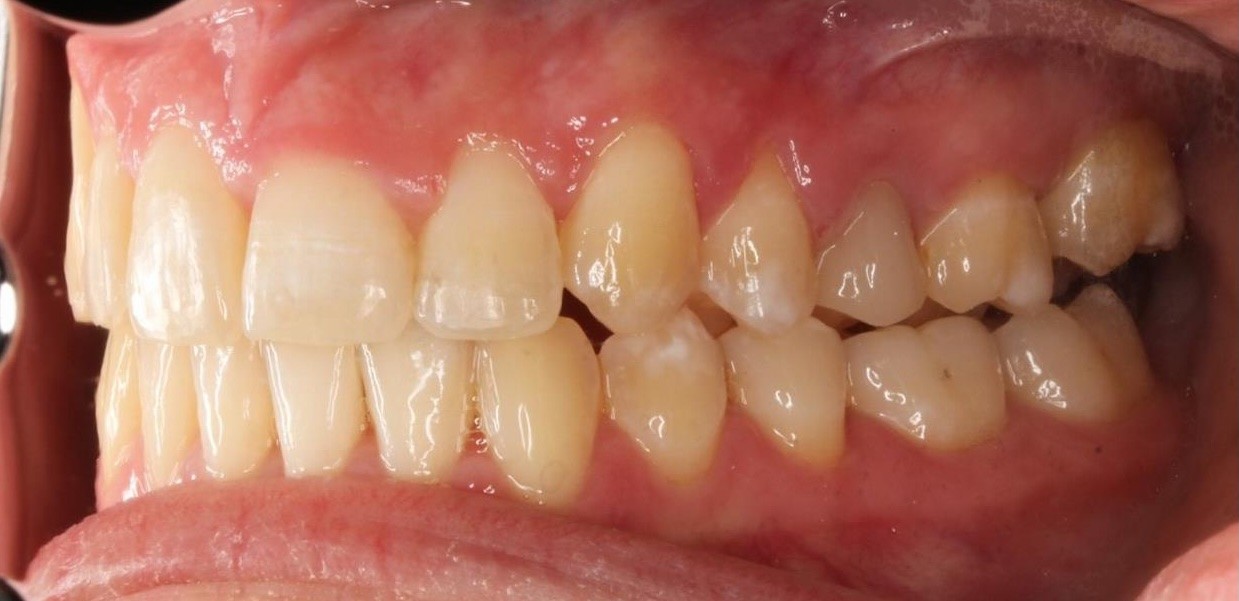

Diganosis: Moderate crowding in both arches, constricted arch forms with anterior and posterior single tooth crossbites, poor smile display

Initial treatment

INTRAORAL